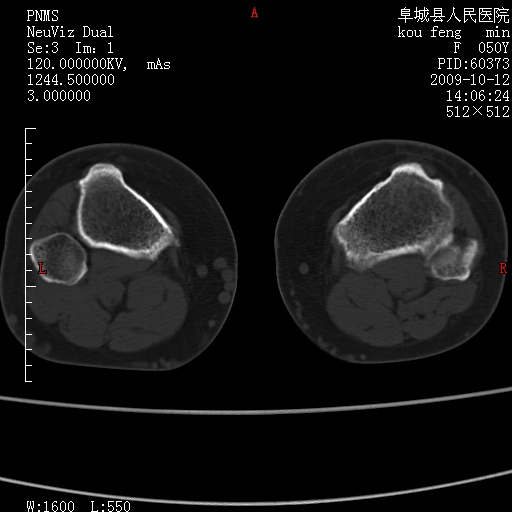

女性,50岁。【请提供患者临床症状体征】

右膝关节退行性改变,关节游离鼠。

右膝关节退行性改变,滑膜黏液囊钙/骨化并游离。

右膝关节退行性改变